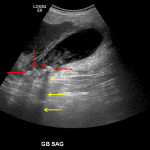

- Multiple gallstones layering in the gallbladder

- Gallbladder is distended with a thickened, hypoechoic wall

- Linear echogenic structures within the gallbladder lumen

- Small amount of pericholecystic fluid

Acute cholecystitis

Cholelithiasis with gallbladder distension, gallbladder wall thickening and edema, pericholecystic fluid, and positive sonographic Murphy sign, consistent with acute cholecystitis.

Linear echogenic structures within the gallbladder lumen may represent sloughed membranes, which if true would raise concern for gangrenous cholecystitis.